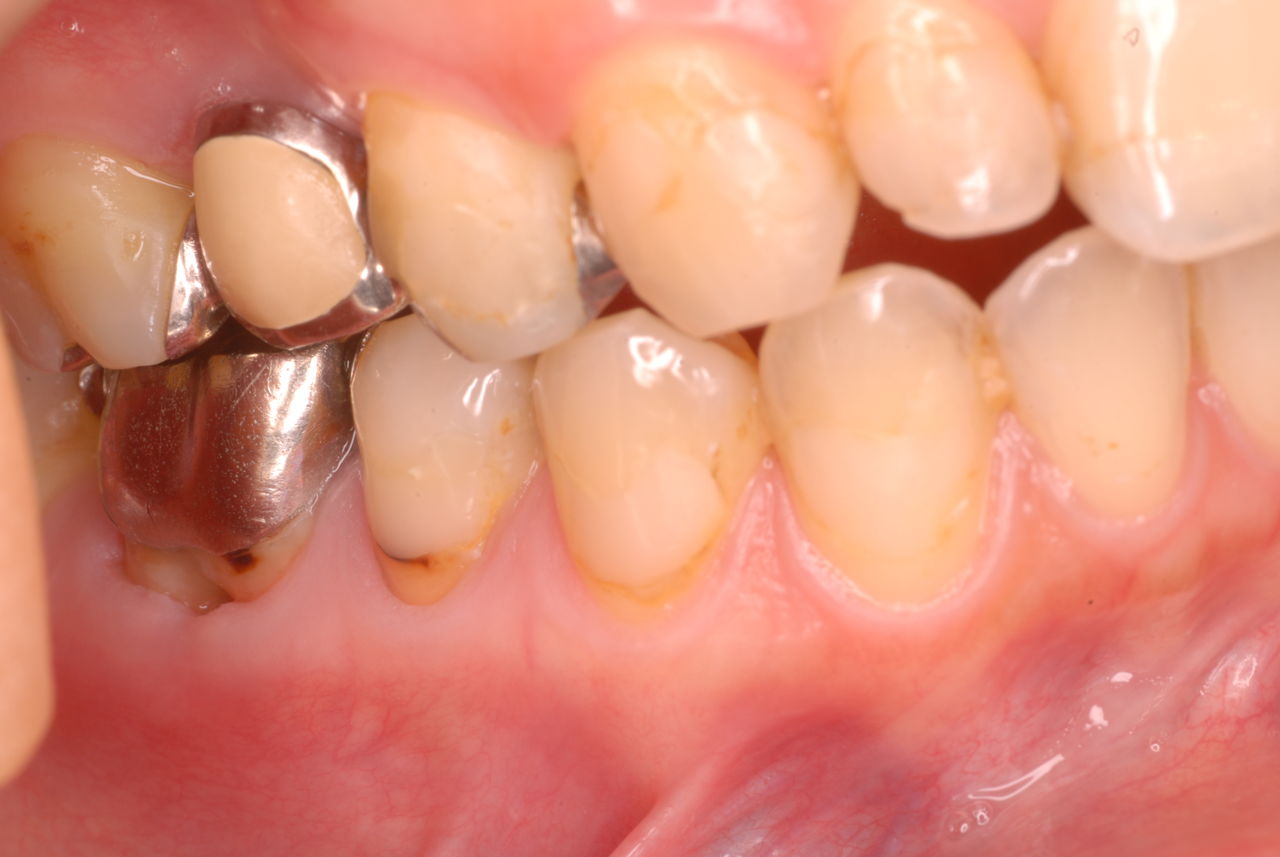

写真左下の親知らずが痛くなり抜歯しました。その後歯茎を除去して虫歯を露出させる処置を二回ほどしています。

治療の成功率は極めて悪くすぐ再発しやすいのです。

隣の14歳大臼歯がひどい虫歯になり治療不可能になりつつある状態のレントゲン